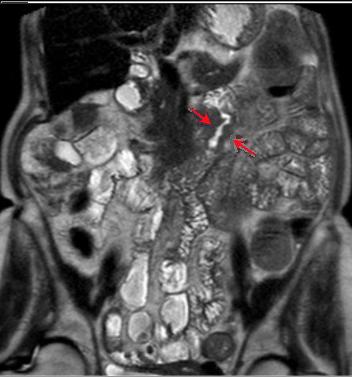

Tumeur adenocarcinoma

duodenum : Image epaissisement circonferentielle de

la paroi avec stenose de la lumiere du duodenum .

Dilatation lergere du duodenum en amont . Image IRM

T1 (fat stranding ) |